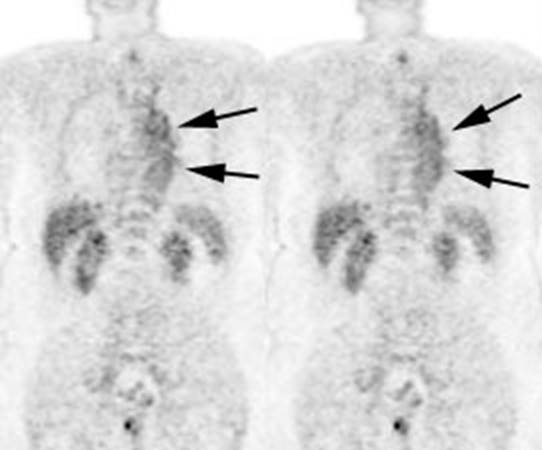

Figure 11 - Brown Fat: Prominent, symmetric

supraclavicular tracer uptake was seen in this patient without a corresponding

CT finding. Uptake in this area has been felt to be related to the presence of

"brown" fat.